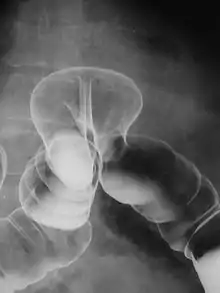

فیزیک پرتوشناسی تشخیصی:[پانویس 3] در این شاخه از فیزیک پزشکی، با مدالیتههایی همچون سی تی اسکن، ام آر آی (تصویر برداری تشدید مغناطیسی)، سونوگرافی، ماموگرافی، فلوروسکوپی، و رادیوگرافی معمولی میتوان سر و کار داشت.[17] فیزیک پرتوشناسی زیرمجموعهٔ این شاخه از فیزیک پزشکی است. طراحی و ضمانت کارکرد صحیح[پانویس 4] و کنترل کیفیت اینگونه دستگاهها بر عهدهٔ متخصصان فیزیک پزشکی میباشد.[18]

ماموگرافی به شیوه امروزی (بهخصوص شیوه آزمایشی[پانویس 43]) نخست در اواخر دهه ۱۹۵۰ در مرکز سرطان ام دی اندرسون دانشگاه تگزاس توسط باب ایگن[پانویس 44] ابداع گردید. او از نوآوریهای خود همانند افزایش mA همزمان با کاهش kVp و نیز استفاده از فیلم تک-امولسیونی در مقالهای در سال ۱۹۵۹ و سپس کتابی با عنوان «ماموگرافی» در سال ۱۹۶۴ پرده برداشت.[72]